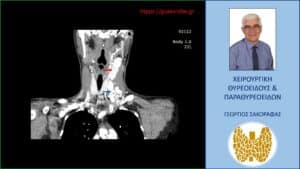

Τα ευρήματα του υπερηχογραφήματος επιβεβαιώθηκαν σε αξονική τομογραφία τραχήλου την οποία προσκομίζει η ασθενής (είχε γίνει πριν το υπερηχογράφημα) (βλ. εικόνες).

Ανάλογη με την προηγούμενη απεικόνιση αλλά σε άλλο επίπεδο στην αξονική τομογραφία. Εμφανής (κόκκινο βέλος) ο πλέον ευμεγέθης παθολογικός λεμφαδένας ψηλά στον τράχηλο (επίπεδο ΙΙ), με το άνω όριό του να είναι σε επαφή με τον αριστερό υπογνάθιο σιελογόνο αδένα. Το μπλε βέλος έχει τοποθετηθεί σε χαμηλότερο επίπεδο εκεί όπου βρίσκεται το ‘συνονθύλευμα’ των πολλαπλών ευμεγέθων παθολογικών λεμφαδένων.